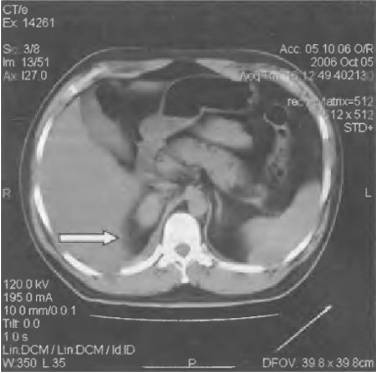

Гидронефроз

Прогрессирующее расширение собирательных полостей почек, которое приводит к их дисфункции.

Характер и локализация боли

Гидронефроз характеризуется ноющими болями в области живота, боков, поясницы и крестца.

При поражении правой почки болезненность ощущается преимущественно справа.

Диагностика и лечение

Диагностировать заболевание можно при помощи анализа крови, УЗИ почек, экскреторной урографии, КТ и МРТ.

- Гидронефроз. Болит здесь часто при расширении лоханки почки. Очень явный признак – моча краснеет, при этом человека тошнит, он страдает от сильного болевого синдрома.